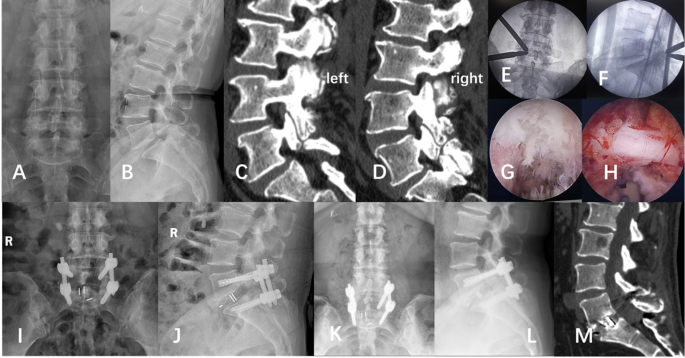

UBE-TLIF: After general anesthesia, the patient was prone on the operating table. Fluoroscopy was used to locate the target intervertebral space and pedicle screw. After the placement of a contralateral percutaneous pedicle screw guidewire, on the affected side, the landmarks of skin incision were 1.5 cm above and below the desired disk level and 1 cm lateral to the edge of the pedicle screw. Guide rods and dilators are inserted step by step, intersecting precisely at the desired disk level. The viewing portal and working portal are inserted, and ablation under endoscopic guidance is used to expose the intersection of the base of the spinous process with the lamina and the lateral facet joints, creating a space on the surface of the lamina. Drilling along the base of the spinous process opens the lower edge of the lamina, a rongeur is used to remove the lamina to expose the upper endpoint of the ligamentum flavum. The lateral lower inferior facet joint is removed, exposes the superior facet joint. After exploring the lateral recess, the tip of the superior facet joint is removed. Along the lateral recess, the lateral and caudal edges of the ligamentum flavum were exposed. After stripping and removing the ligamentum flavum along its cranial, lateral, and caudal edges, the ipsilateral dural sac and nerve roots were exposed. After exploring and protecting nerve roots on the affected side, the nucleus pulposus protrusion was examined. Part of the posterior longitudinal ligament and annulus fibrosus was excised, removing the nucleus pulposus. Expanders inserted gradually, the cartilaginous endplate scraped away, the endplate surface was explored under the scope. Autologous bone and artificial bone were placed in the intervertebral space, and a cage of appropriate size was inserted under vision. Four percutaneous pedicle screws were inserted, and rods were placed for fixation. Irrigation and suture were performed. (Fig. 2)

UBE-TLIF: A 63-year-old woman complained about lower back pain for 5 years, worsening over the past 3 months accompanied by radiating pain in both lower extremities. Intermittent claudication has worsened pain at rest. (A and B) Lateral and AP fluoroscopic view; (C and D). The lumbar CT in the sagittal plane indicates a bilateral spondylolysis at L5; (E and F). Intraoperative lateral and AP fluoroscopic view; (G and H). Endoscopic view; (I and J). Postoperative day 2 lumbar spine AP and lateral view; (K and L). 3 months postoperative lumbar spine AP and lateral view; (M) 5 months postoperative sagittal plane of lumbar CT.